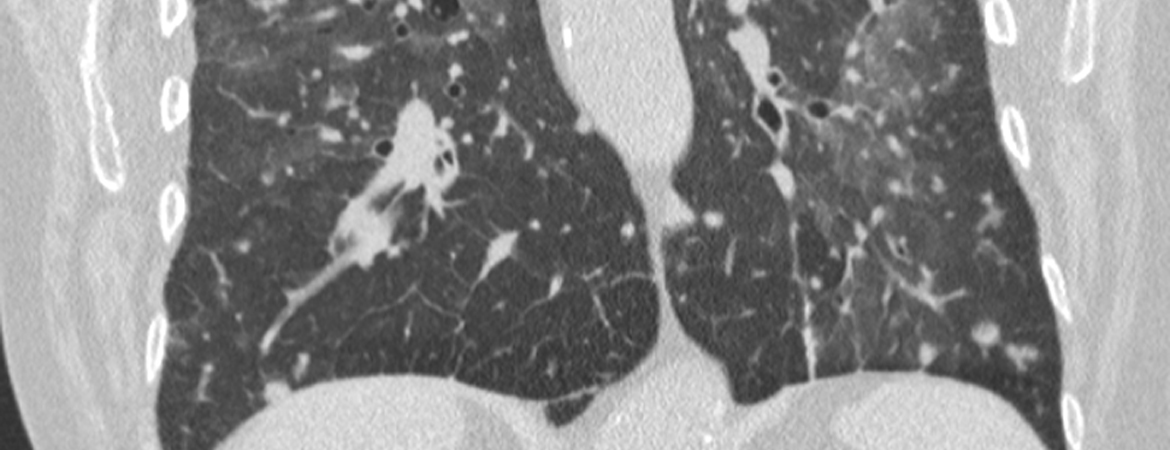

Elia Rigamonti, Davide Salera, Alina C. Gheorghiu, Corneliu Fratila, Pietro Gianella (Author) The many faces of interstitial pneumonia: a case of presumed SARS-CoV-2 infection Fulltext PDF Fulltext HTML